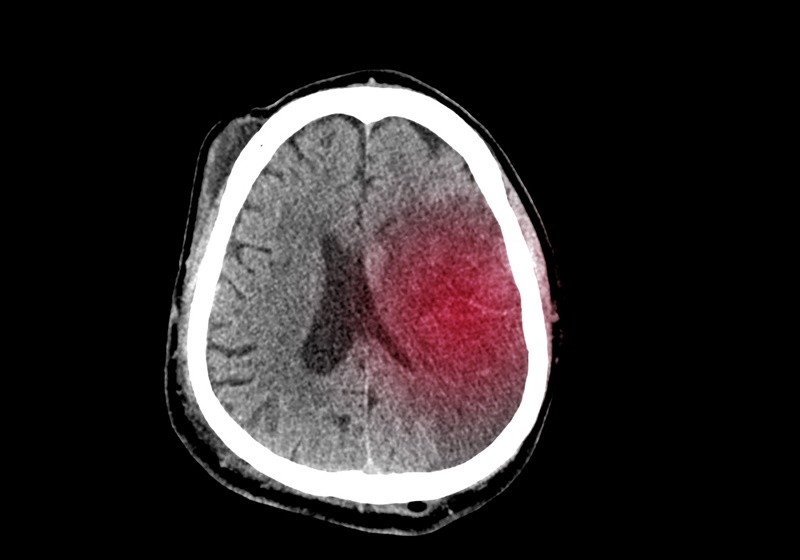

최근 날씨 변화와 스트레스로 인해 고혈압 환자가 증가하면서, 뇌출혈 발생 위험도 덩달아 높아지고 있다. 뇌출혈은 뇌혈관이 파열되면서 뇌 안에 출혈이 생기는 질환으로, 단 몇 분 만에 생명을 위협할 수 있는 중증 뇌질환 중 하나다.

뇌출혈은 크게 외상성 뇌출혈과 자발성 뇌출혈로 나뉜다. 외상성은 교통사고나 낙상처럼 외부 충격으로 인해 발생하며, 자발성은 고혈압, 뇌혈관 기형, 뇌동맥류 파열, 항응고제 복용 등으로 인해 예고 없이 발생한다. 전체 뇌졸중의 약 10~15%를 차지하지만, 사망률은 더 높고 후유증도 심각해 주의가 필요하다.

전문의들은 조기 진단과 빠른 치료가 무엇보다 중요하다고 강조한다. CT나 MRI 같은 뇌 영상 검사를 통해 출혈의 위치와 양을 확인하고, 상황에 따라 수술적 치료가 필요한 경우도 많다. 특히 뇌 안 깊은 곳에서 출혈이 일어난 경우, 내시경이나 미세 수술 기법을 이용해 혈종을 제거하고 뇌압을 낮추는 수술이 진행된다.